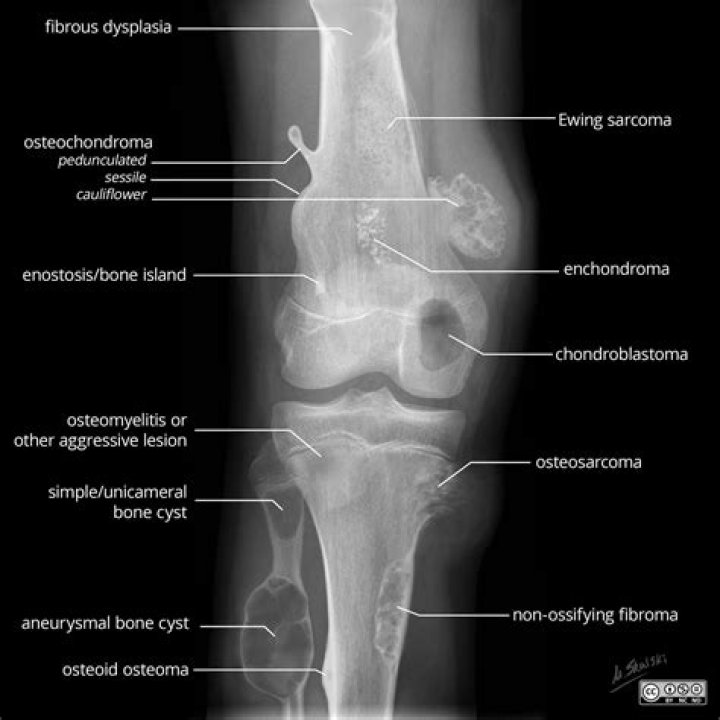

What does osteochondroma look like?

An osteochondroma looks like a bony projection on the external surface of a bone, like a bony mushroom on a stalk, usually near a growth plate area. It can occur in any bone but is seen most often around the knee or upper arm. This tumor generally grows with the child and stops growing once the child completes puberty.

Osteochondroma is an overgrowth of cartilage and bone that happens at the end of the bone near the growth plate. Most often, it affects the long bones in the leg, the pelvis, or the shoulder blade. Osteochondroma is the most common noncancerous bone growth.

An osteochondroma is a cartilage-covered bony excrescence (exostosis) that arises from the surface of a bone. Osteochondromas, which are the most common bone tumors in children, may be solitary or multiple, and they may arise spontaneously or as a result of previous osseous trauma.

What does osteochondroma mean in medicine?